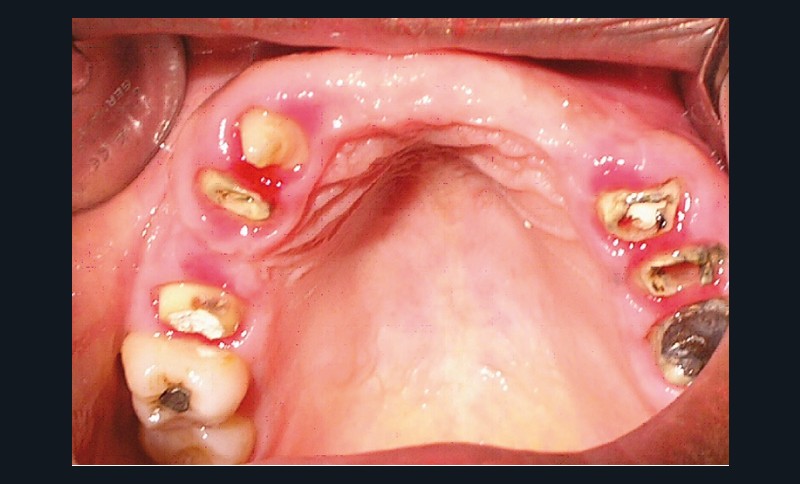

La patiente a été porteuse d’un bridge céramo-métallique de onze éléments au maxillaire pendant huit mois (fig. 1, 2), puis d’un bridge transitoire au maxillaire (fig. 3). Elle signale quelques rares épisodes de saignement probablement dus à l’irritation par la prothèse. Cette dernière se descelle couramment, créant ainsi un préjudice fonctionnel, esthétique et psychologique.

- Examen endobuccal : l’hygiène buccale est satisfaisante. Cependant, nous notons la présence d’un bridge transitoire fracturé au niveau de la 13 (fig. 3).

L’examen dentaire ne montre pas de mobilité dentaire. À l’arcade maxillaire, les dents 11, 14, 21, 22, 23 sont absentes. Les dents 13, 15, 24, 25 sont à l’état de racine (fig. 4). Nous notons des reconstitutions coronaires à l’amalgame sur les 26 et 16. À l’arcade mandibulaire, les dents 37, 36, 46, 47 sont absentes et une obturation coronaire à l’amalgame sur 38 est en place. Les bords libres du groupe incisivo-canin et les cuspides des prémolaires sont légèrement abrasés (fig. 5).

La collecte des données physiques et complémentaires révèle, au maxillaire, l’existence d’un édentement de classe III Kennedy-Applegate, modification 1 (antérieure) et un important délabrement coronaire de la 15, 13, 23, 24 ; à la mandibule, la présence d’un édentement de classe III Kennedy-Applegate, modification 1.